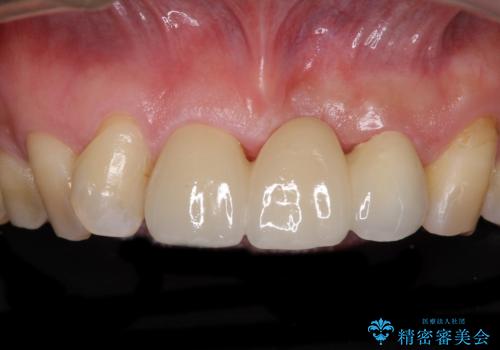

変色した前歯 オーダーメイドタイプのオールセラミッククラウン

変色した前歯のオールセラミック治療